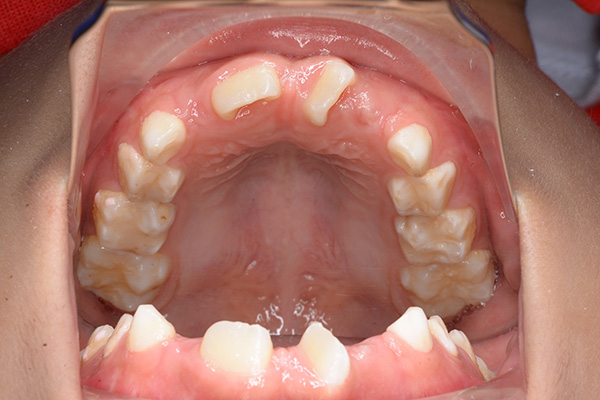

| 主訴 | 上顎前歯のでこぼこ | 診断名 | アングルⅡ級叢生症例 | ||||

|---|---|---|---|---|---|---|---|

| 初診時年齢 | 6歳9ヵ月 | 性別 | 男 | 動的治療期間 | 6ヵ月 | ||

| 既往歴として上顎正中過剰歯(2本)は抜去済み。その影響で上顎右側中切歯は捻転して萌出しており、下顎右側中切歯と早期接触が認められたため2x4(上顎のみブラケット装着)にて前歯部の改善を行った。現在は永久歯列完成まで経過観察を行い、希望があれば口元の突出感を改善するために本格矯正治療を行うことにしている。 | |

| セファロ所見 | 上下顎骨は調和のとれた位置関係を示していたが、頭蓋に対して両顎共に前方に位置していた。上下顎前歯は唇側傾斜していた。 |